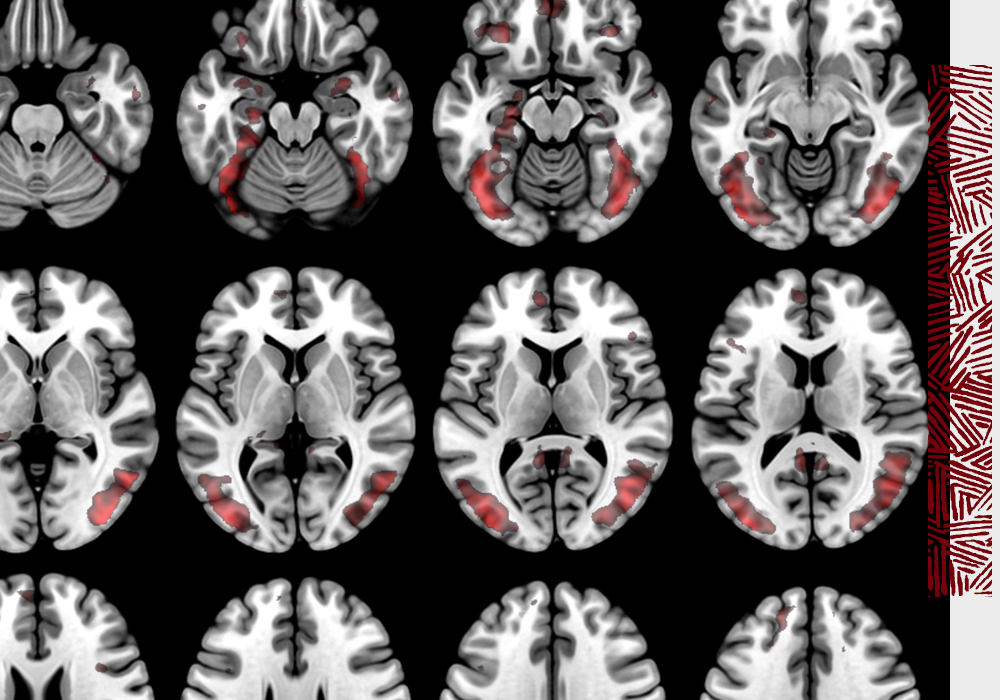

As a psychology professor and co-director of the university’s McCausland Center for Brain Imaging, Chris Rorden has made his mark with the open-source software he developed to assist in brain visualization, image processing and statistics.

“My seminal image processing work has allowed tools designed to look at the healthy brain to be translated to clinical applications,” Rorden says. “This has provided new insights on stroke recovery and helped guide brain stimulation.”

The visualization software has proven valuable throughout the field of neuroscience, and is used for understanding healthy brain function and for mapping the location and extent of brain injuries.